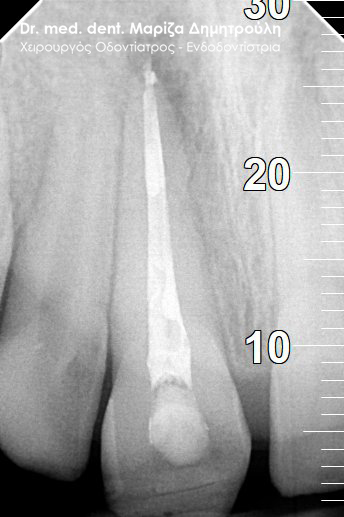

Ο ασθενής επισκέφτηκε το ιατρείο, γιατί πονούσε στον πάνω δεξί κεντρικό τομέα την τελευταία εβδομάδα. Στο δόντι είχε πραγματοποιηθεί απονεύρωση πριν 4 χρόνια. Επιθυμία του ήταν η διατήρηση του δοντιού στο στόμα. Η οδοντίατρος που είχε πραγματοποιήσει την απονεύρωση πριν χρόνια, του πρότεινε εξαγωγή του δοντιού και τοποθέτηση εμφυτεύματος.

Κλινικά η περιοχή γύρω από τον κεντρικό τομέα ήταν πρησμένη και εξερχόταν πύον από την ουλοδοντική σχισμή. Το δόντι είχε στεφάνη .Ο ασθενής με δική του πρωτοβουλία είχε ξεκινήσει τη λήψη αντιβίωσης.

Μετά τον ακτινογραφικό έλεγχο διαπιστώθηκε οτι η παλιά απονεύρωση ήταν ελλιπής/ ατελής στο άκρο της ρίζας του δοντιού.

Μετά απο συνεννόηση με τον ασθενή αποφασίστηκε να γίνει μία προσπάθεια διατήρησης της στεφάνης του δοντιού και παράλληλα να πραγματοποιηθεί επανάληψη της απονεύρωσης του δοντιού.

Μετά την χορήγηση τοπικής αναισθησίας τοποθετήθηκε ελαστικός απομονωτήρας (λάστιχο) και έγινε διάνοιξη του δοντιού μέσω της στεφάνης. Στη στεφάνη δημιουργήθηκε γλωσσικά μία τρύπα ώστε να διατηρηθεί η θήκη του δοντιού, ενώ ταυτόχρονα να είναι δυνατή η αφαίρεση του παλιού εμφρακτικού υλικού στη ρίζα του δοντιού. Στη συνέχεια ξεκίνησε η επανάληψη της ενδοδοντικής θεραπείας (απονεύρωση) με την αφαίρεση του παλιού εμφρακτικού υλικού σε όλο το μήκος της ρίζας του δοντιού. Ακολούθησε η επεξεργασία του δοντιού με μηχανοκίνητα εργαλεία και οι διακλυσμοί ( έκπλυση ) στο εσωτερικό της ρίζας για την απομάκρυνση των νεκρών οδοντικών ιστών / κυττάρων και την απολύμανση της ρίζας. Έγινε τοποθέτηση φαρμάκου και έγινε προγραμματισμός για τη συνέχιση της απονεύρωσης σε επόμενο ραντεβού.

Εφόσον ο ασθενής δεν πονούσε, το οίδημα στην περιοχή είχε υποχωρήσει και το δόντι ήταν ασυμπτωματικό ακολούθησε η ολοκλήρωση της απονεύρωσης με την έμφραξη της ρίζας του δοντιού.

Το σημείο της στεφάνης που τροχίστηκε γλωσσικά έκλεισε με σφράγισμα σύνθετης ρητίνης. Αυτή ήταν μία συμβιβαστική λύση σε συνεννόηση με τον ασθενή, προκειμένου το δόντι να παραμείνει στο στόμα και να μην εξαχθεί.

ΠΡΙΝ

ΜΕΤΑ